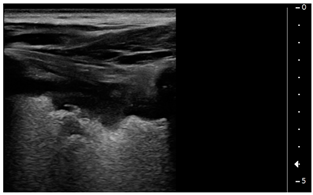

- Pleural effusion: Anechoic or hypoechoic collection external to lung parenchyma, typically in a dependent lung region with or without respiratory movement of the lung within the effusion (flapping lung)

- Consolidations > 1 cm with or without pleural effusion (Table 1).

Interestingly, the finding of subpleural and lobar consolidations with or without pleural effusion was associated with a lower LVEF on admission and need for inotrope use; also, presence of a LUS pattern of subpleural consolidations was associated with PICU length of stay.

Our patients showed the presence of subpleural consolidations or consolidations with or without pleural effusion correlating with the degree of heart failure (LVEF at admission and need for inotropes), and this is a new finding. Subpleural consolidations are common in COVID-19 pneumonia in children [8] and have also been described in asymptomatic pediatric patients [30,31]. It is possible that this pattern in MIS-C patients refers to sequelae of the primary infection that had not been detected during initial SARS-CoV-2 infection but was still present at time of MIS-C diagnosis. It is also possible that they are expressions of the inflammatory state that these patients show through fever and elevated markers of inflammation [32]. The correlation of subpleural consolidations with PICU length of stay could also be interpreted under this light as a sign of a more severe disease. MIS-C is a novel entity that follows the primary infection with COVID-19 in children which is still under investigation under different aspects. The inflammatory state in this disease seems caused from a cytokine storm that causes fever, elevation of all markers of inflammation and multiorgan failure, with activation of T cells, macrophages, natural killer cells and overproduction of immune or non-immune defense cells, and the release inflammatory cytokines and chemical mediators. Endothelial cell dysfunction follows, resulting in damage to the microvascular system and abnormal activation of the coagulation system, resulting in systemic small vessel vasculitis and extensive microthrombosis [33]. Therefore, it is possible to speculate that the pattern we found on LUS is a possible expression of a mix of pathological events on the lung parenchyma, a consequence of both the cardiogenic edema and a direct inflammatory/micro-embolic lung disease.

It is reported that elevation of ferritin is of negative prognostic value in patients with MIS-C as an index of hyper-inflammation state [40]. In our series ferritin levels are higher in LUS pattern 5, as if the presence of consolidations and/or effusion was due to the inflammatory vasculitic process with the production of pleuric exudative fluid.